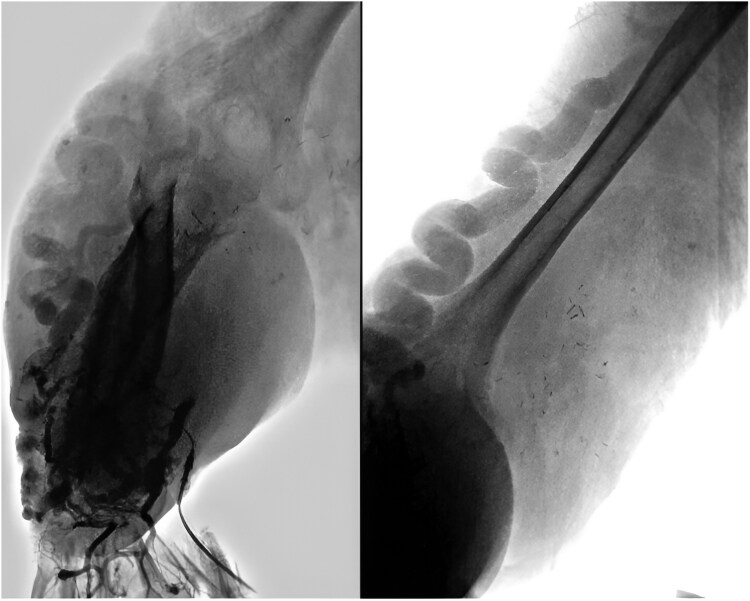

Case report: A 33-year-old male with a long-standing, progressively enlarging AVM of the right upper limb presented with necrosis and haemorrhage, leading to hypovolemic shock. Angiography revealed an AVM involving the subclavian, axillary, and brachial arteries, necessitating embolization and surgical interventions. Six years later, he developed distal finger necrosis, requiring infracondylar amputation. He later presented with stump infection, purulent discharge, orthopnoea, jugular venous distension, a loud second heart sound, and a holosystolic murmur in the tricuspid region. Echocardiography and catheterization confirmed PAH and a high-flow arteriovenous fistula. Multidisciplinary evaluation led to definitive amputation and PAH treatment. Postoperatively, PAH resolved, and the patient was discharged with ongoing follow-up, showing significant improvement.